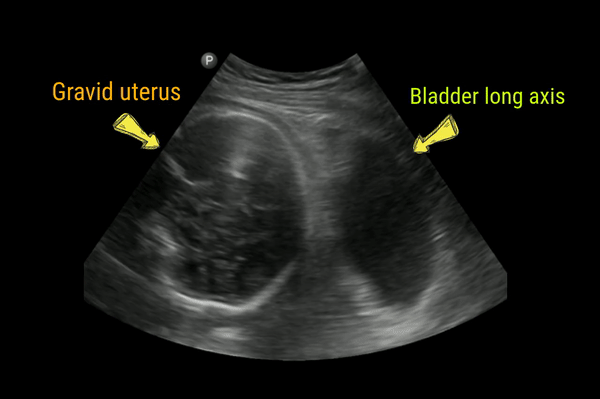

Right sided predominance may be due to dextrorotation of the uterus by the sigmoid colon, kinking of the ureter as it crosses the right iliac artery, and/or proximity to the right ovarian vein. Following figure gives an idea of the anatomy.

In these cases, it is often difficult to trace the ureter to the point of obstruction. However, in pathologic hydronephrosis, one may visualize the source of obstruction (e.g. stone). In addition, if the pelvic diameter exceeds 10 mm, pathologic dilatation should be suspected.